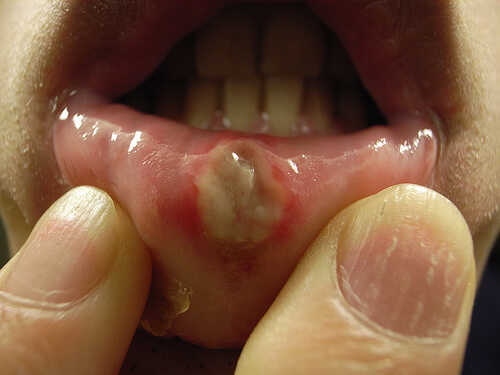

Objawami występowania owrzodzenia w jamie ustnej jest: pieczenie, bolesne mrowienie, okrągłe rany w kolorze białym lub szarym z zaczerwieniami na krawędziach. W przypadku owrzodzenia może też wystąpić gorączka, obrzęk węzłów chłonnych, itp.